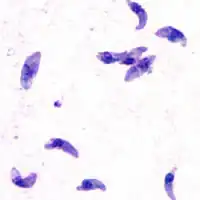

![]() Токсоплазмы при оптической микроскопии | |